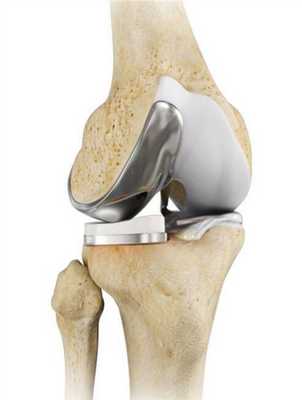

Упрощенная схема установки импланта.

Единственная тактика лечения, которая дает результаты - эндопротезирование. Индустрия выпускает модернизированные имплантаты под требования любого пациента. Искусственные конструкции создаются из биосовместимых материалов, представленных керамикой, инновационными сплавами металлов и высокомолекулярным полиэтиленом, которые не оказывают токсического, аллергического и канцерогенного воздействия на окружающие структуры.

Самый распространенный тип импланта коленного сустава.